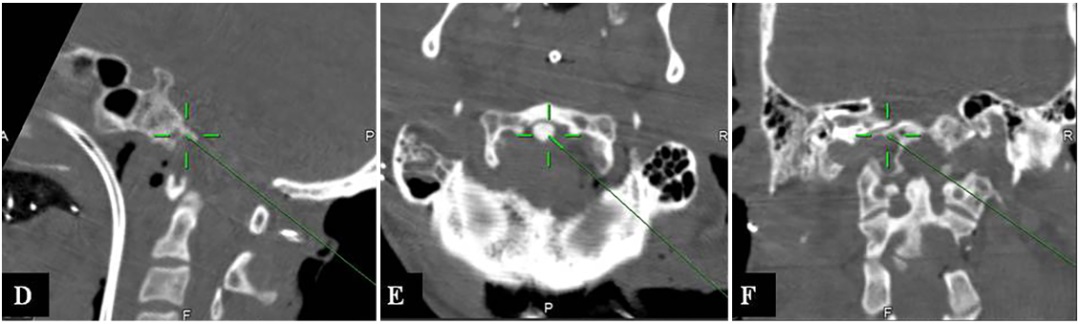

▼通过右侧内镜辅助远外侧经髁入路(EA-FLTA)切除颅颈交界处残余肿瘤(33.4 cm³)(图4D-F)。然后,进行枕颈融合术(OCF)(C0-C3-C4-C5)。

D-F:术中在CT引导神经导航下,进行EA-FLTA入路手术,显示进入斜坡(D)、齿状突(E)和对侧OC(F)的手术操作可行性。

▼术后MRI显示NTR(图4G-I)。

图片G-I:术后MR显示椎前、下斜坡和椎后的肿瘤被切除。